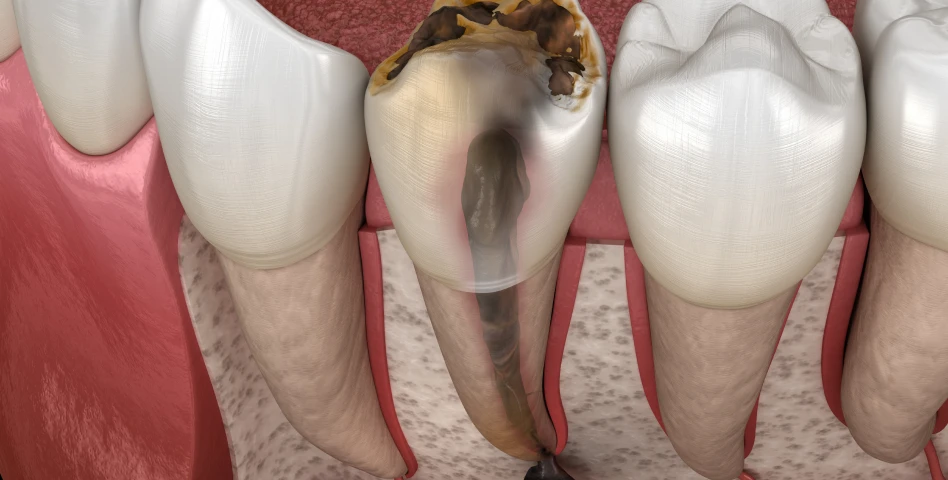

Non, l’intervention se fait sous anesthésie locale. Les suites post-opératoires sont généralement légères.

La chirurgie dure en moyenne 30 à 60 minutes par implant. Une phase de cicatrisation de quelques mois est souvent nécessaire avant la prothèse.